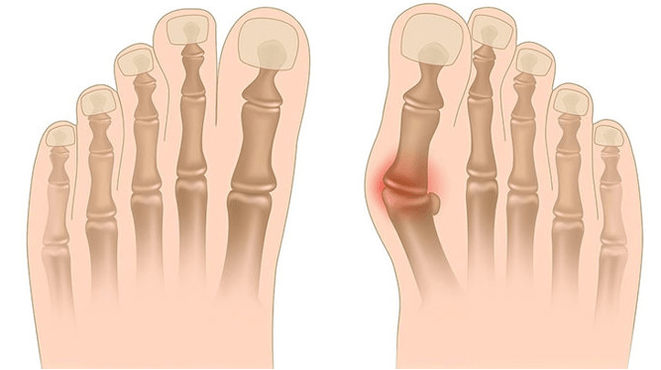

La deformazione di Valgus è la curvatura del piede, che è caratterizzata dall'appiattimento del suo arco longitudinale. In genere, il bordo interno del piede viene abbassato ("caduta") e il tallone risulta.

Se prendi i piedi (se lo guardi da dietro), una deformazione simile a X si forma a livello della caviglia: le caviglie sono in contatto, mentre i tacchi sono separati a una distanza da 5 a 6 centimetri.

- I - Non ci sono deformazioni ossee, il dolore è determinato sulla superficie interna della caviglia (nell'area di fissare il muscolo tibiale posteriore).

- II - Curvatura della luce, il tallone è leggermente respinto;

- III - Il piede viene assegnato e la deformazione viene determinata (non correttamente corretta);

- IV - La curvatura è osservata non solo nel piede, ma anche nell'articolazione della caviglia.

Nella terza fase, viene determinato il piombo dell'osso scongelato (notevolmente inferiore alla caviglia sulla superficie interna della caviglia) e una forte deviazione del tallone all'aperto (il paziente si trova sul bordo interno dell'osso del tallone).